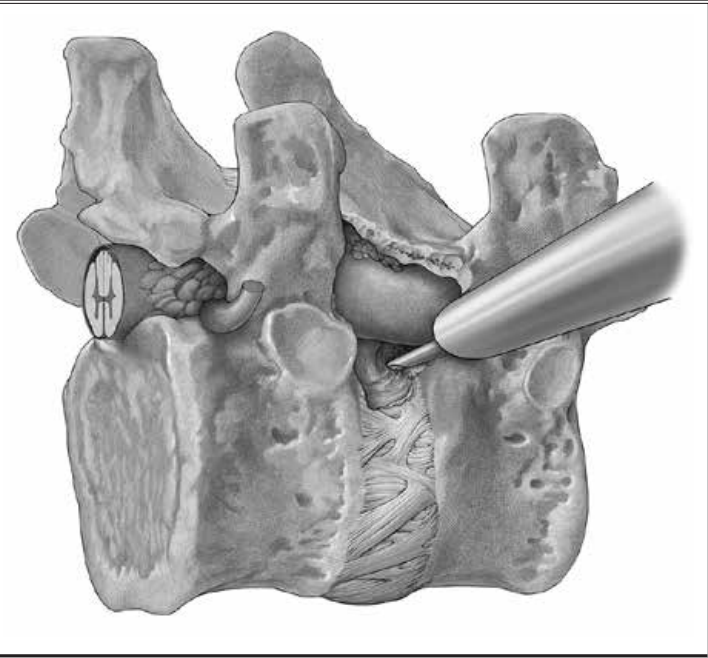

两手指的技术,分离内脏鞘和血管鞘,根据病变的位置建立工作通道。

4.作7mm皮肤切口,触摸T1椎体前缘,插入克氏针后置入环钻,方向为从前上到T1-2的后方。

环钻上骨质,使用c臂确认工作套管位置